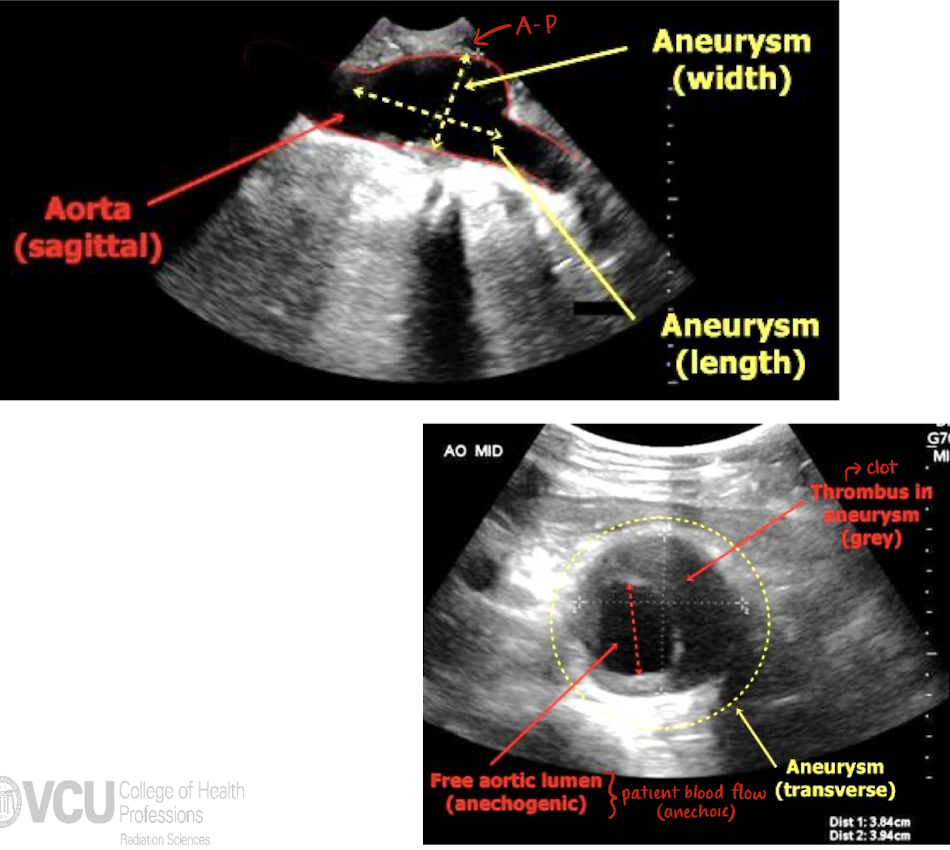

abdominal aortic aneurysm (AAA)

permanent localized dilation of AO when diameter is greater than 1.5x the proximal AO or is more than 3 cm

primary risk factors: dissection (3 types) and rupture

tx: surgical repair via graft placement

what should a sonographer note when they see a AAA?

size (L x W x H in LONG and TRANS)

shape (fusiform or saccular)

location (infrarenal?)

is there wall thickening, calcification, blood flow, or plaque?